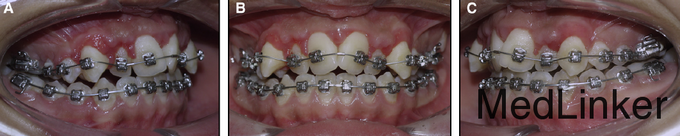

直面型,上颌严重横向不调伴严重拥挤(拥挤度17mm),前牙及双侧后牙反合,下牙列重度拥挤,左侧磨牙I类,右侧磨牙II类关系,双侧尖牙II类关系。劲椎片可见其已过生长发育期

诊断:上牙弓严重横向不调。治疗:上颌颊侧骨皮质切开术+固定矫治+上颌腭侧固定扩弓。上颌上拖槽一周后行骨皮质切开术,如图,切开后全层翻瓣暴露骨皮质,于骨皮质上打孔,范围从牙槽骨顶端下方2mm到根尖下方2mm。根据牙槽厚度孔的深度从0.5mm到1.5mm不等,复位后间断缝合。同时腭侧粘接由带环,螺旋扩弓器制作的固定扩弓装置,即刻加力,转动完整的一圈。之后每周扩弓器打开1mm,连续8周,上颌牙弓被打开,扩弓器再维持2月,同时固定矫治器继续排齐整平。总疗程5个月2周。上颌宽度变化第一前磨牙间增加10mm,第二前磨牙间增加8.9mm,第一磨牙间增加8.3mm。但尖牙间宽度不变,这也是为什么扩弓后后期牙弓能够保持的原因,尖牙间宽度对维持牙弓稳定性非常重要。